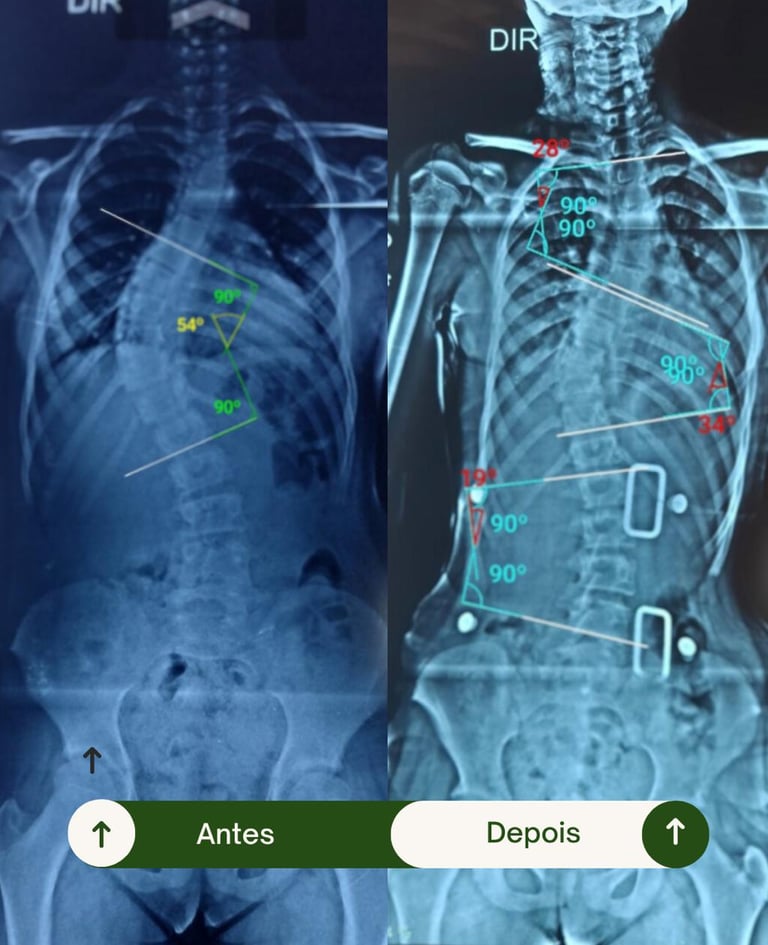

Resultados Comprovados

Transformando vidas por meio da fisioterapia e da tecnologia 3D.

Veja como nossos pacientes reconquistaram mobilidade, conforto e confiança.